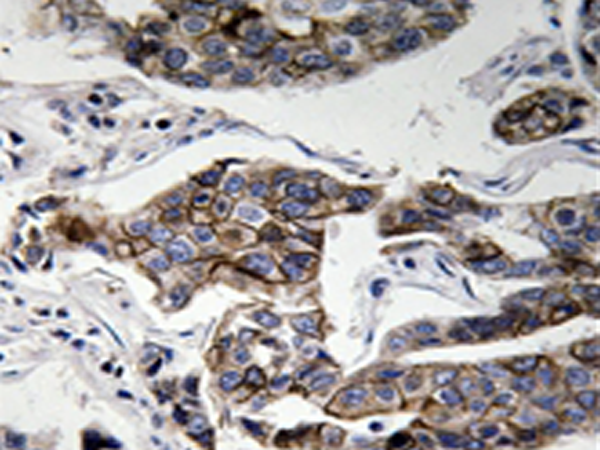

IHC positive control: |

Human breast carcinoma tissue |

IHC Recommend dilution: |

50-100 |